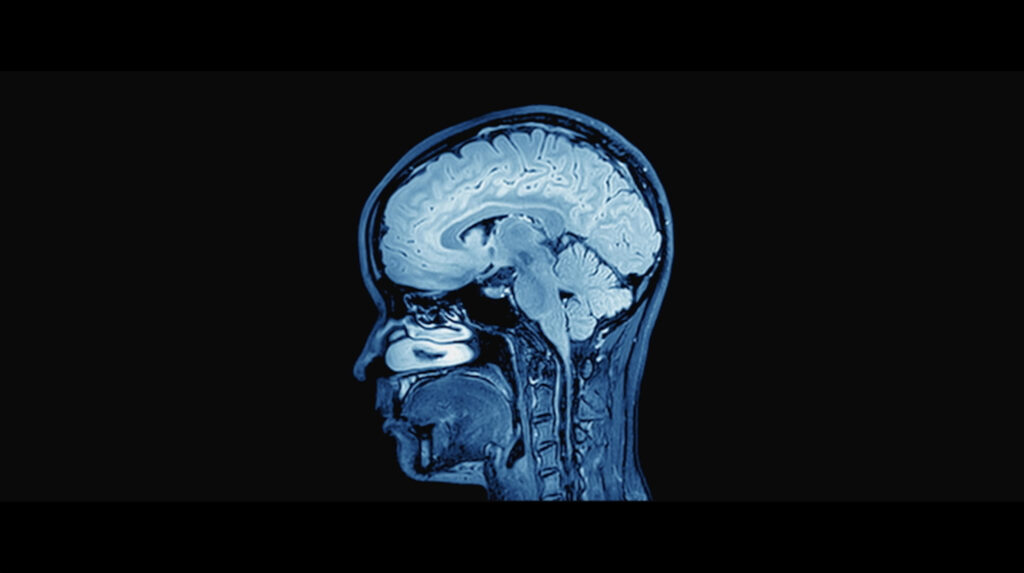

“Minds Wide Open” created for the Chen Institute and broadcast globally on Discovery Channel, is an award-winning documentary that has reached and inspired millions of viewers around the world. The film takes audiences on a powerful journey into the cutting edge of neuroscience, exploring the mysteries of the human brain with depth, humanity, and cinematic flair.